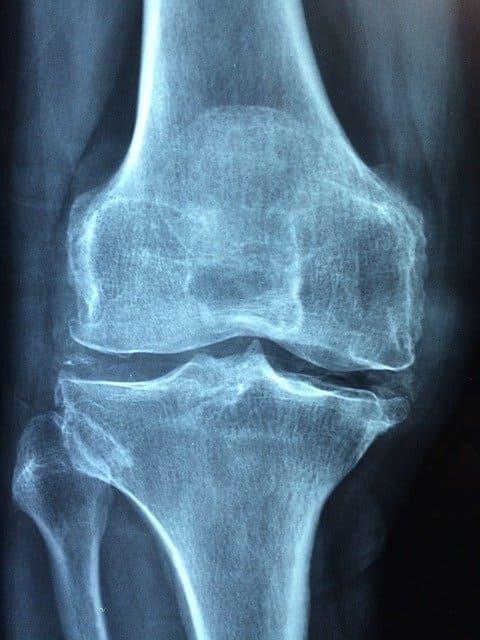

脱臼は、関節を形成している骨が完全に離れた状態のこと

脱臼は、関節を形作っている骨が完全に離れてしまった状態のことです。脱臼が起きると、骨と骨をつないでいる関節部分の骨が本来の位置からずれてしまうのです。

脱臼は程度によって、骨が関節から完全に離れた状態の完全脱臼と部分的に骨が関節から離れていて完全に離れている状態ではない亜脱臼に分けられます。

一般的に脱臼が起きる部位は腕や脚、顎や首、脊椎、肘や股などです。脱臼した部位には痛みや腫れが起こることが多く、あざやゆがみや曲がり、ずれなどが起こることもあります。